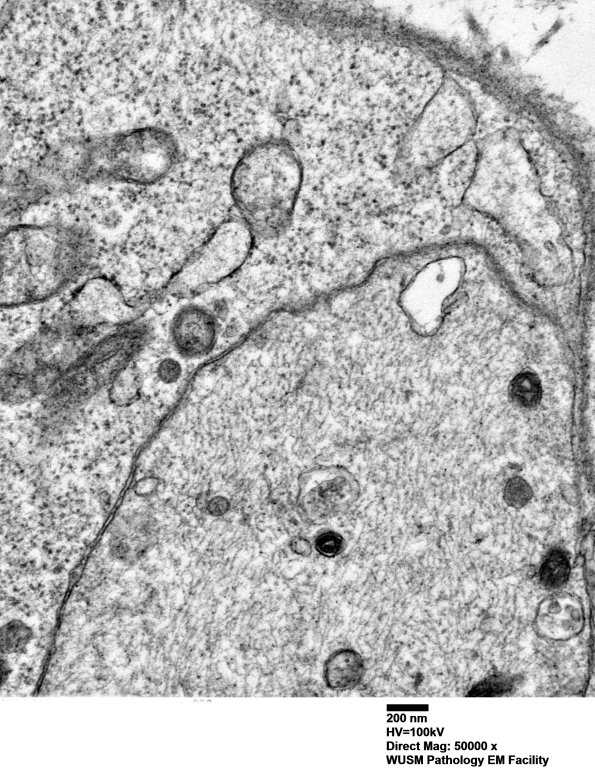

4F5B (Case 4) Ant Interosseus nerve_036 - Copy

A higher magnification of image #4F5A. (electron micrograph)